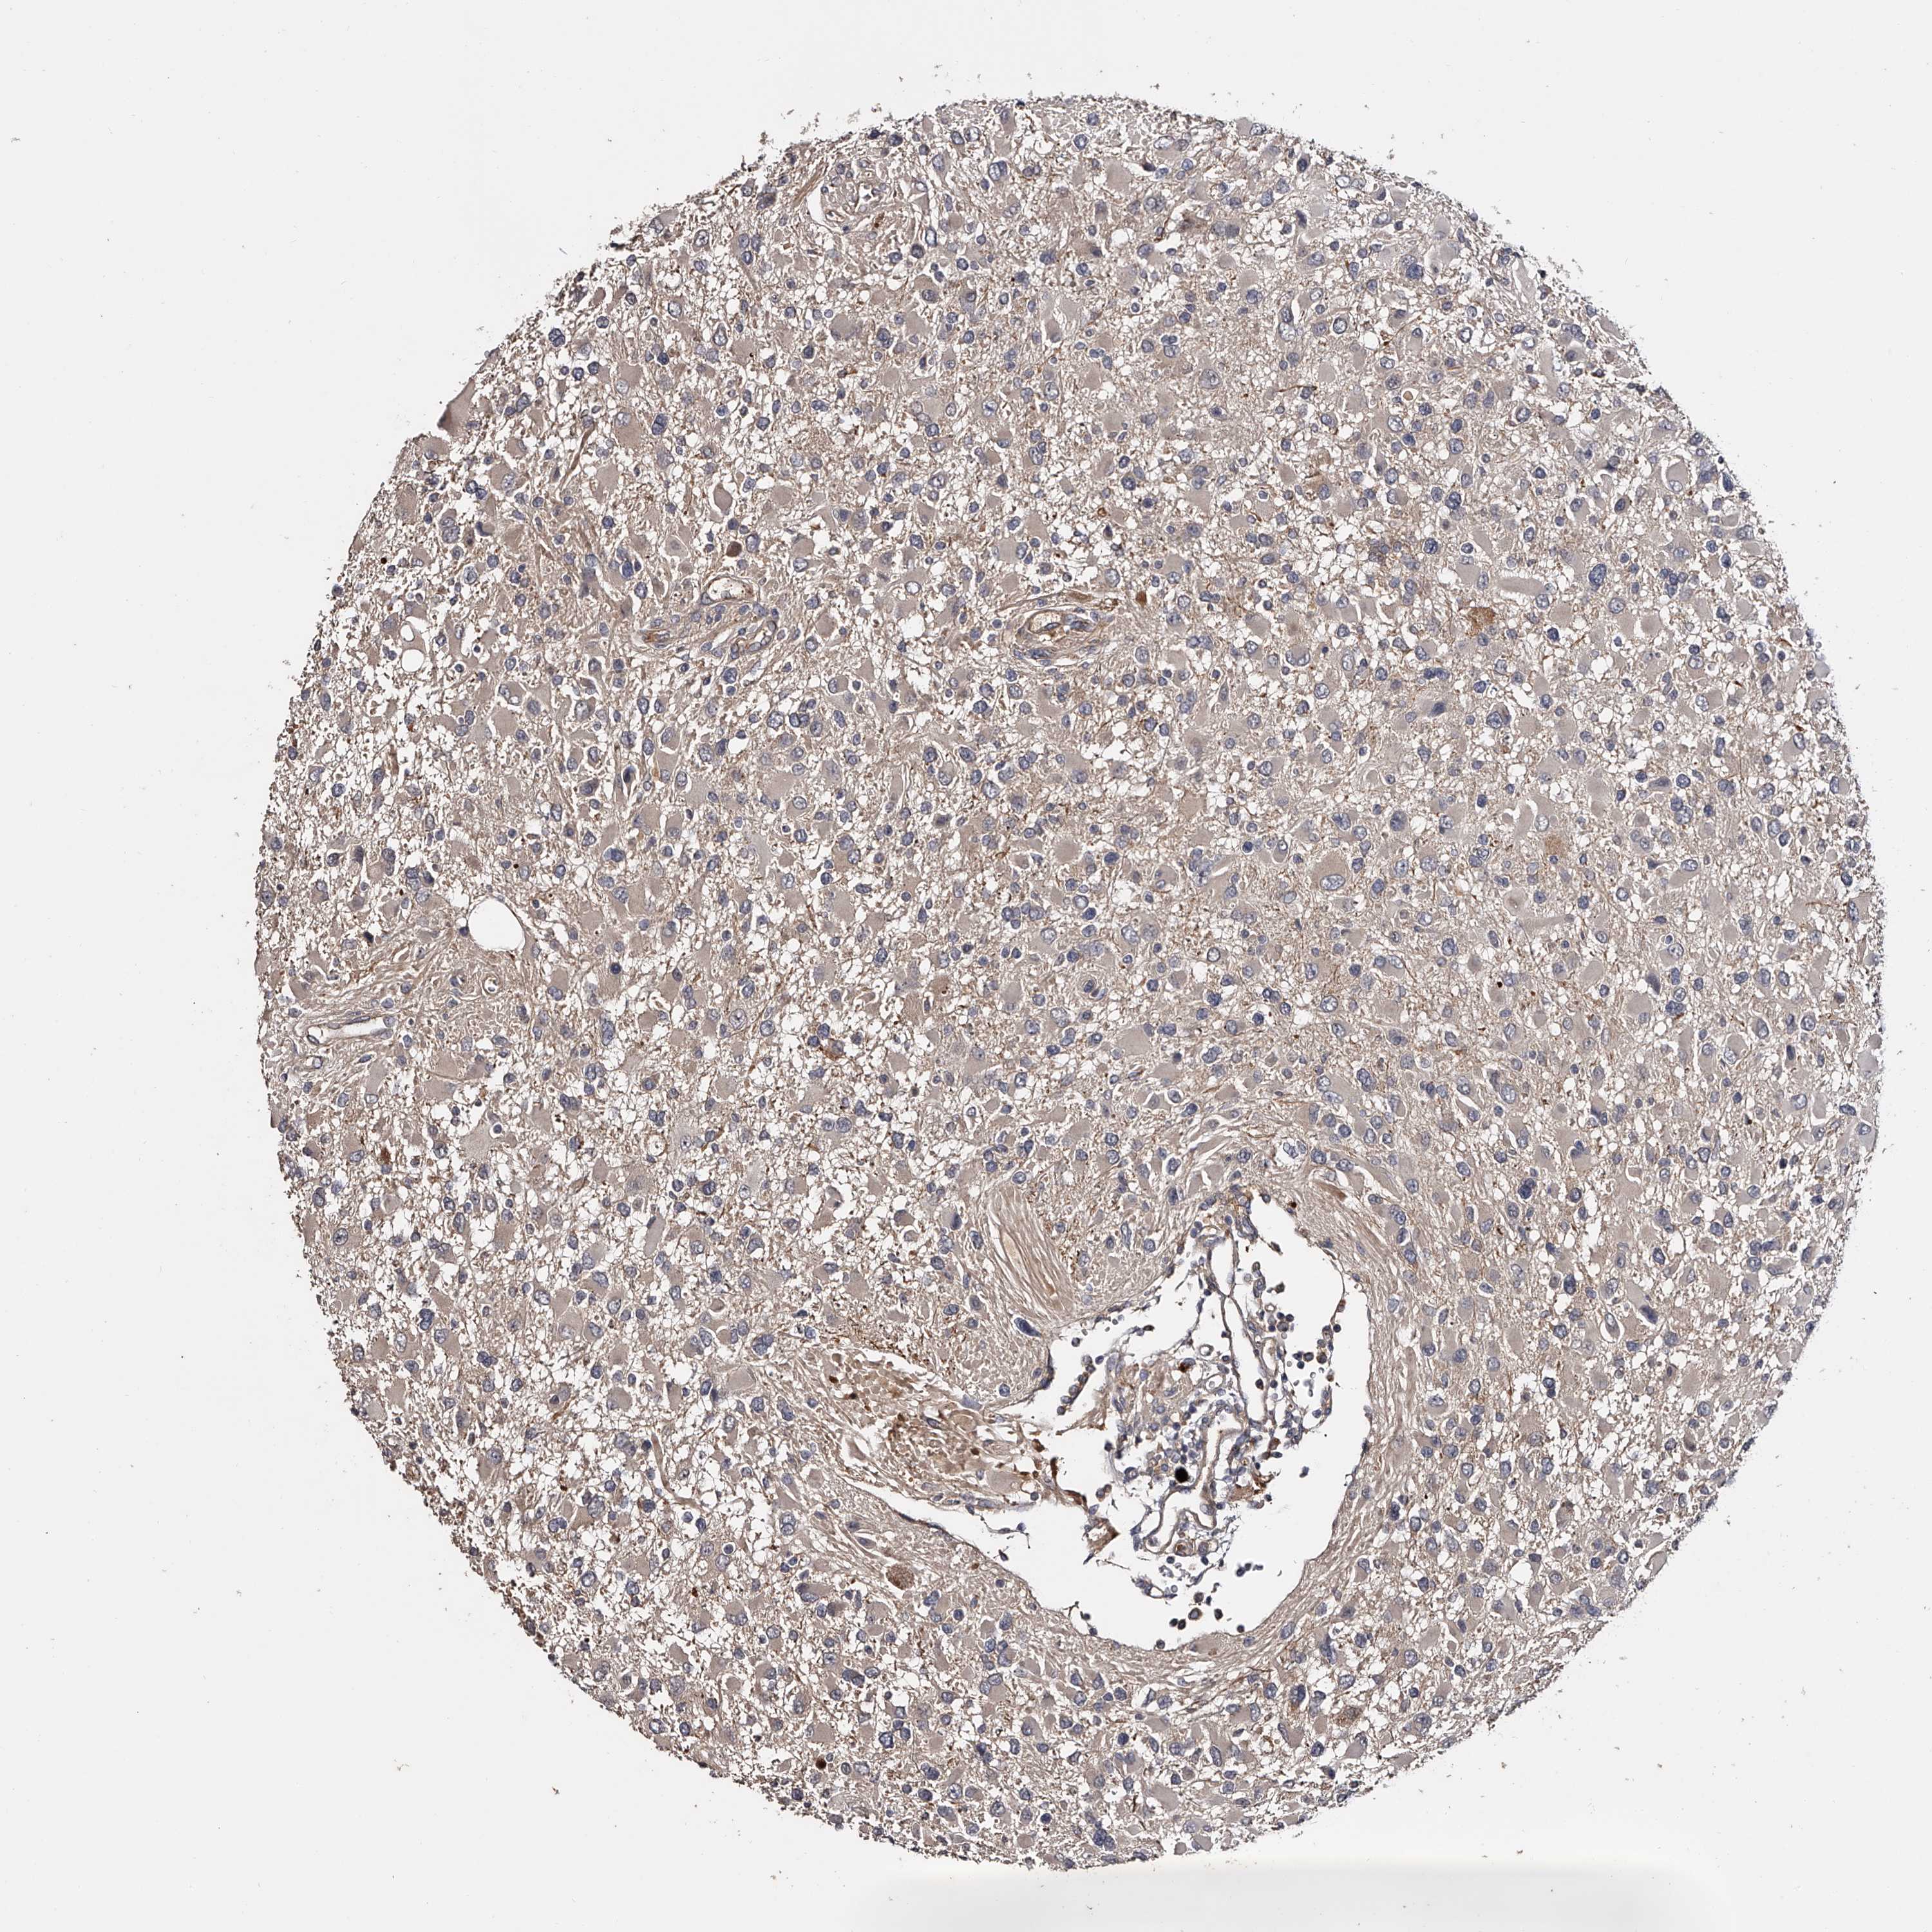

GLIOMA - Protein expressioni

A mouse-over function shows sample information and annotation data. Click on an image to view it in a full screen mode. Samples can be filtered based on level of antibody staining by selecting one or several of the following categories: high, medium, low and not detected. The assay and annotation is described here.

Note that samples used for immunohistochemistry by the Human Protein Atlas do not correspond to samples in the TCGA dataset.

Antibody stainingi

Antibody staining in the annotated cell types in the current human tissue is reported as not detected, low, medium, or high, based on conventional immunohistochemistry profiling in selected tissues. This score is based on the combination of the staining intensity and fraction of stained cells.

Each image is clickable and will lead to virtual microscopy that enables deeper exploration of all samples and also displays staining intensity scores, fraction scores and subcellular localization as well as patient and tissue information for each sample.

Antibody HPA029666

Antibody HPA029667

Antibody HPA029668

Antibody HPA029669

Glioma, malignant, High grade

Glioma, malignant, Low grade

Glioblastoma, NOS